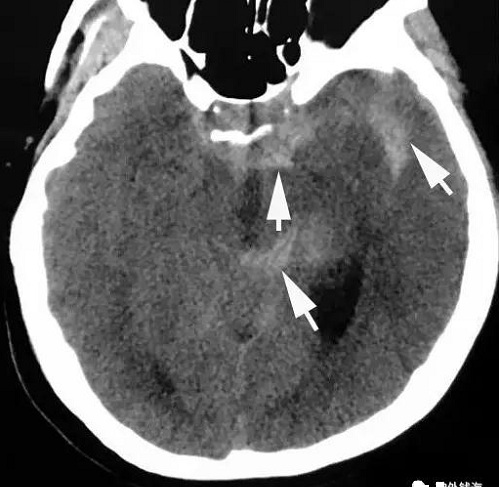

上图为一例43岁女性患者,突发剧烈头痛2天。在当地医院行头颅CT检查可见蛛网膜下腔出血,如箭头所示。